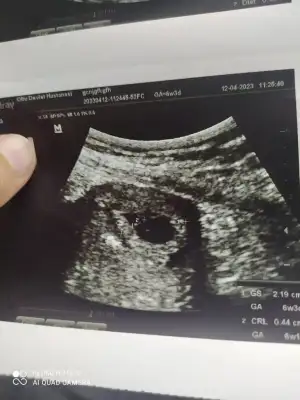

Benim kese görüntüsü bana çok düzgün gibi gelmedi ama doktor moral bozmamak için mi birşey söylemedi acaba yoksa ben mi evham yapıyorum?

Benim kesem de göz gibi devlette gittiğim doktor olumsuz bir şeyin ceyreginin çeyreği bile olsa gözünü kırpmadan pat diye söyler umursamaz yani o yüzden senin kesen bana bozuk gelmedi bu da benim kesem canını sıkma hic

Ne dedi doktor bu arada kese büyüklüğü ne?

Kese büyüklüğünü tam olarak bilmiyorum ultrason fotoğrafında yazıyorsa o var keseyi gösterdi dikkat et gibi şeyler söyledi kan alındı 10 gün sonra tekrar gidecez tahlil sonuçlarında da enfeksiyon var gözüküyor 😔